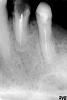

sergnew Опубликовано 8 сентября, 2012 Поделиться Опубликовано 8 сентября, 2012 Что можно сделать с этими зубами?Можно ли вставить штифт с коронкой? Ссылка на комментарий

shishok Опубликовано 9 сентября, 2012 Поделиться Опубликовано 9 сентября, 2012 Мало информации,нужно ещё смотреть состояное зубов в полости рта и общую картину. Ссылка на комментарий